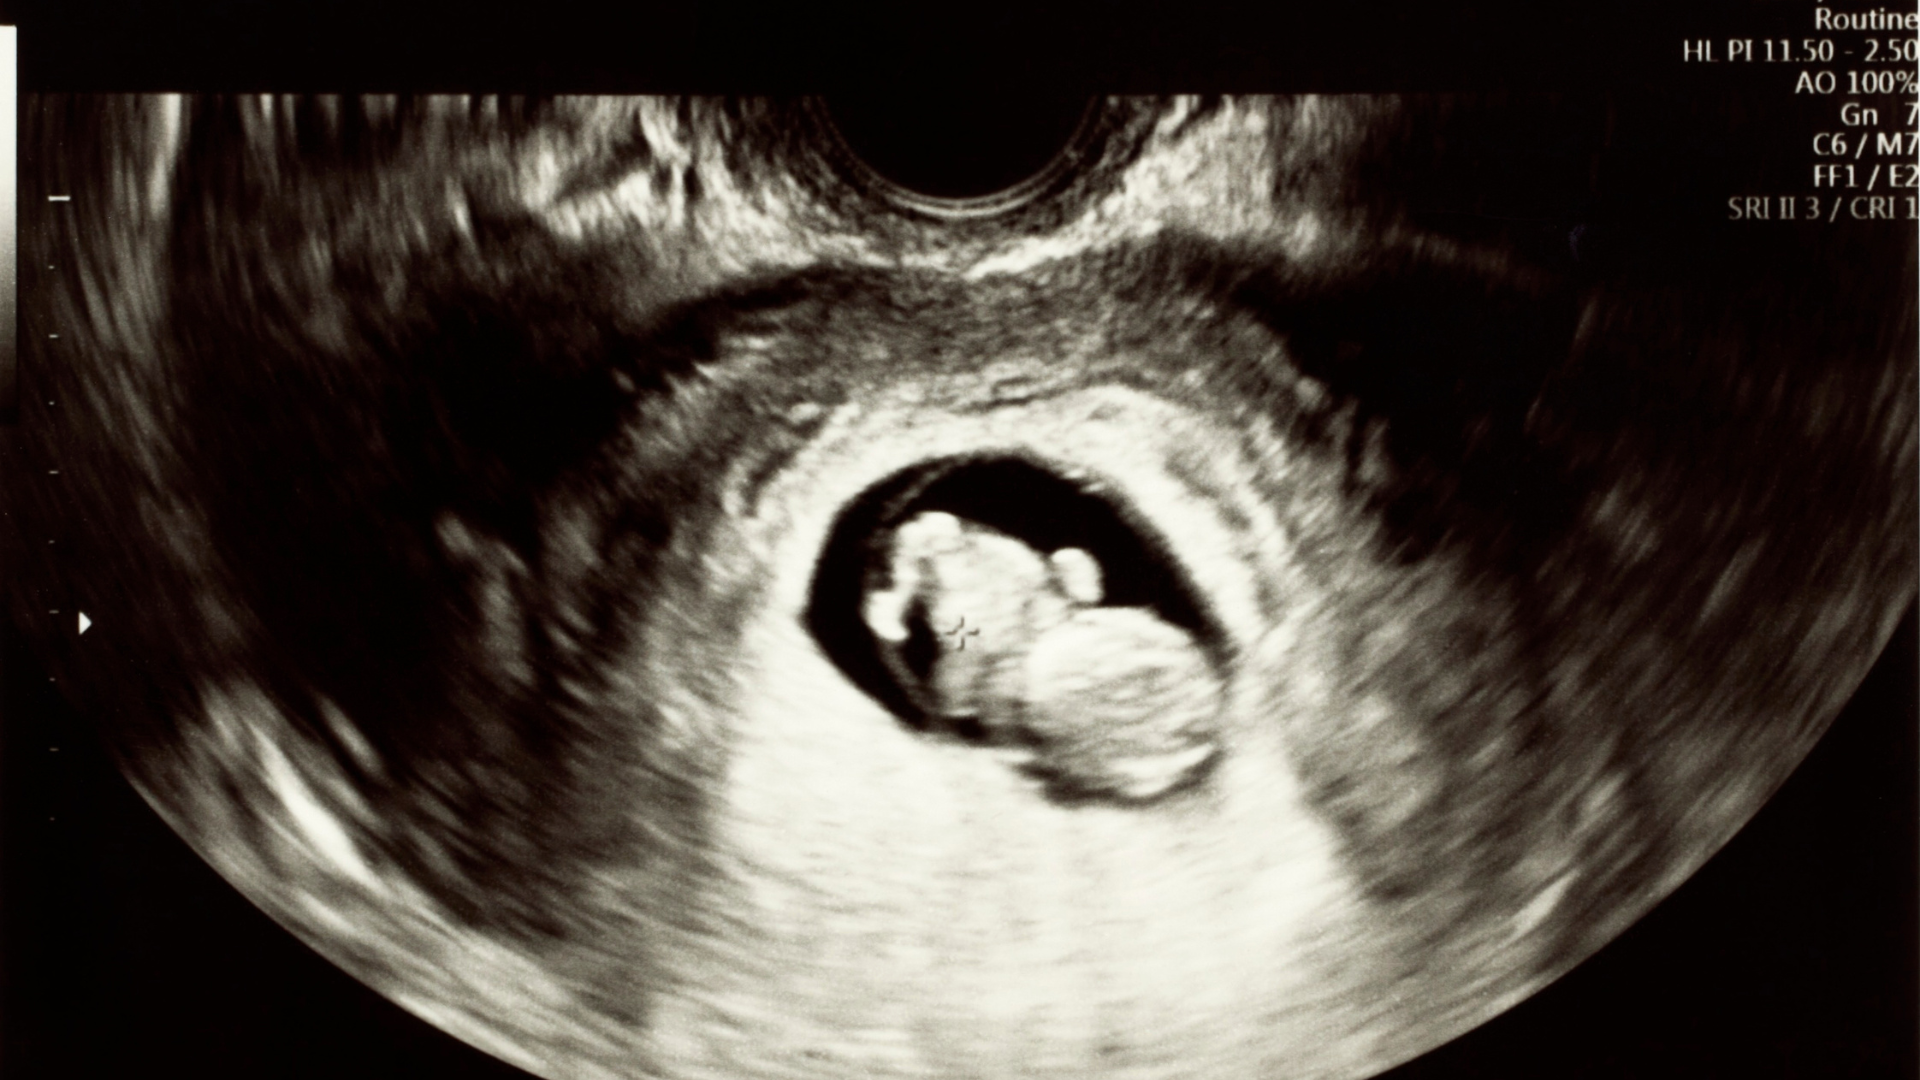

- Siêu âm cho thấy lượng nước ối thấp: Chỉ số AFI giảm, buồng ối hẹp, các phần thai áp sát thành tử cung.

Siêu âm là tiêu chuẩn vàng để chẩn đoán thiểu ối 3 tháng đầu.